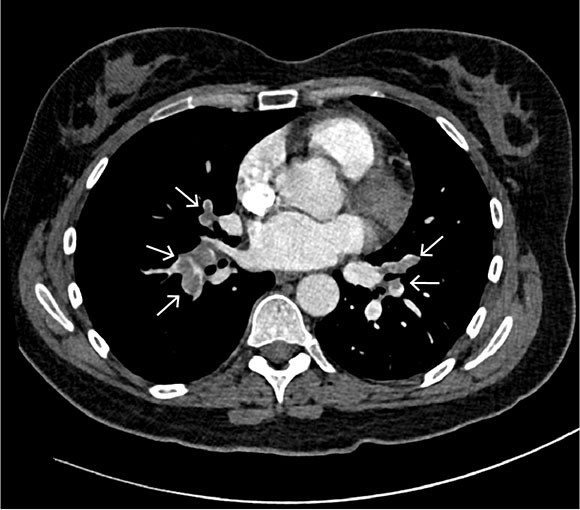

Based on the working diagnosis, CT pulmonary angiography was performed, revealing pulmonary emboli in the right main artery and in segmental and subsegmental pulmonary arteries bilaterally (Figure 1). In both the right and left lung, basal, peripheral, wedge-shaped pulmonary opacities indicative of lung infarctions were observed. Mild dilation of the pulmonary trunk of 34 mm was also revealed, further supporting the suspicion of elevated pulmonary pressure and right ventricular strain.